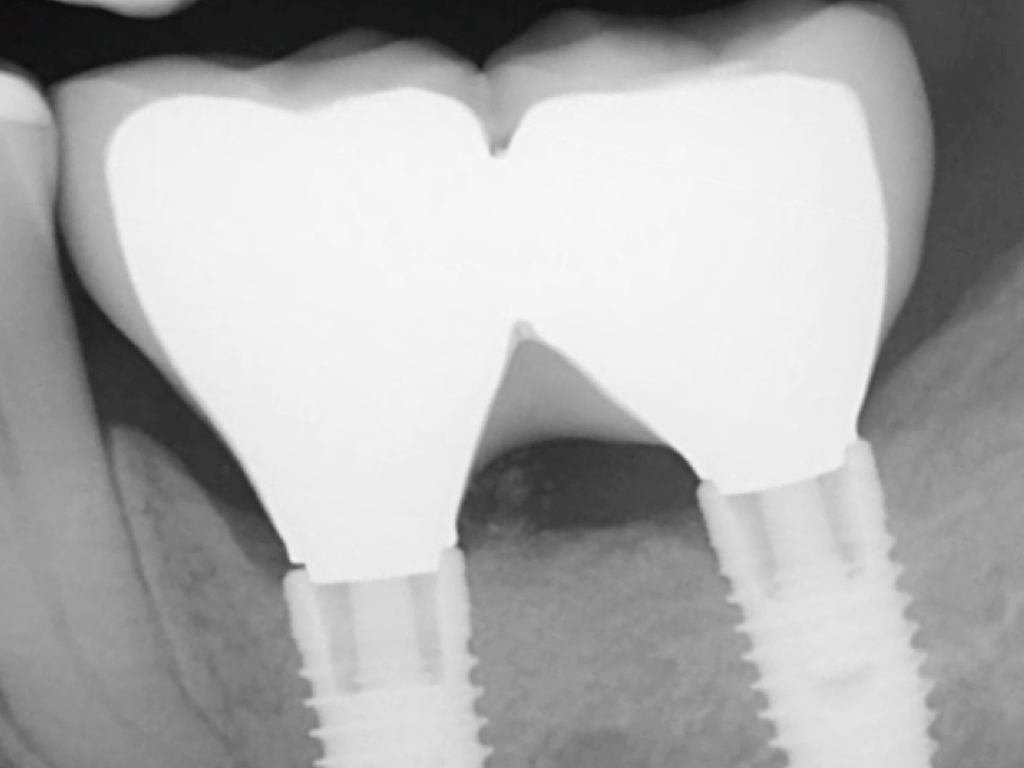

Fig 4. Increased probing depth around an implant with BoP indicates presence of peri-implant disease and the need for taking a radiograph.

Fig 5. Bone loss shown on radiograph confirms the presence of peri-implantitis and peri-mucositis.